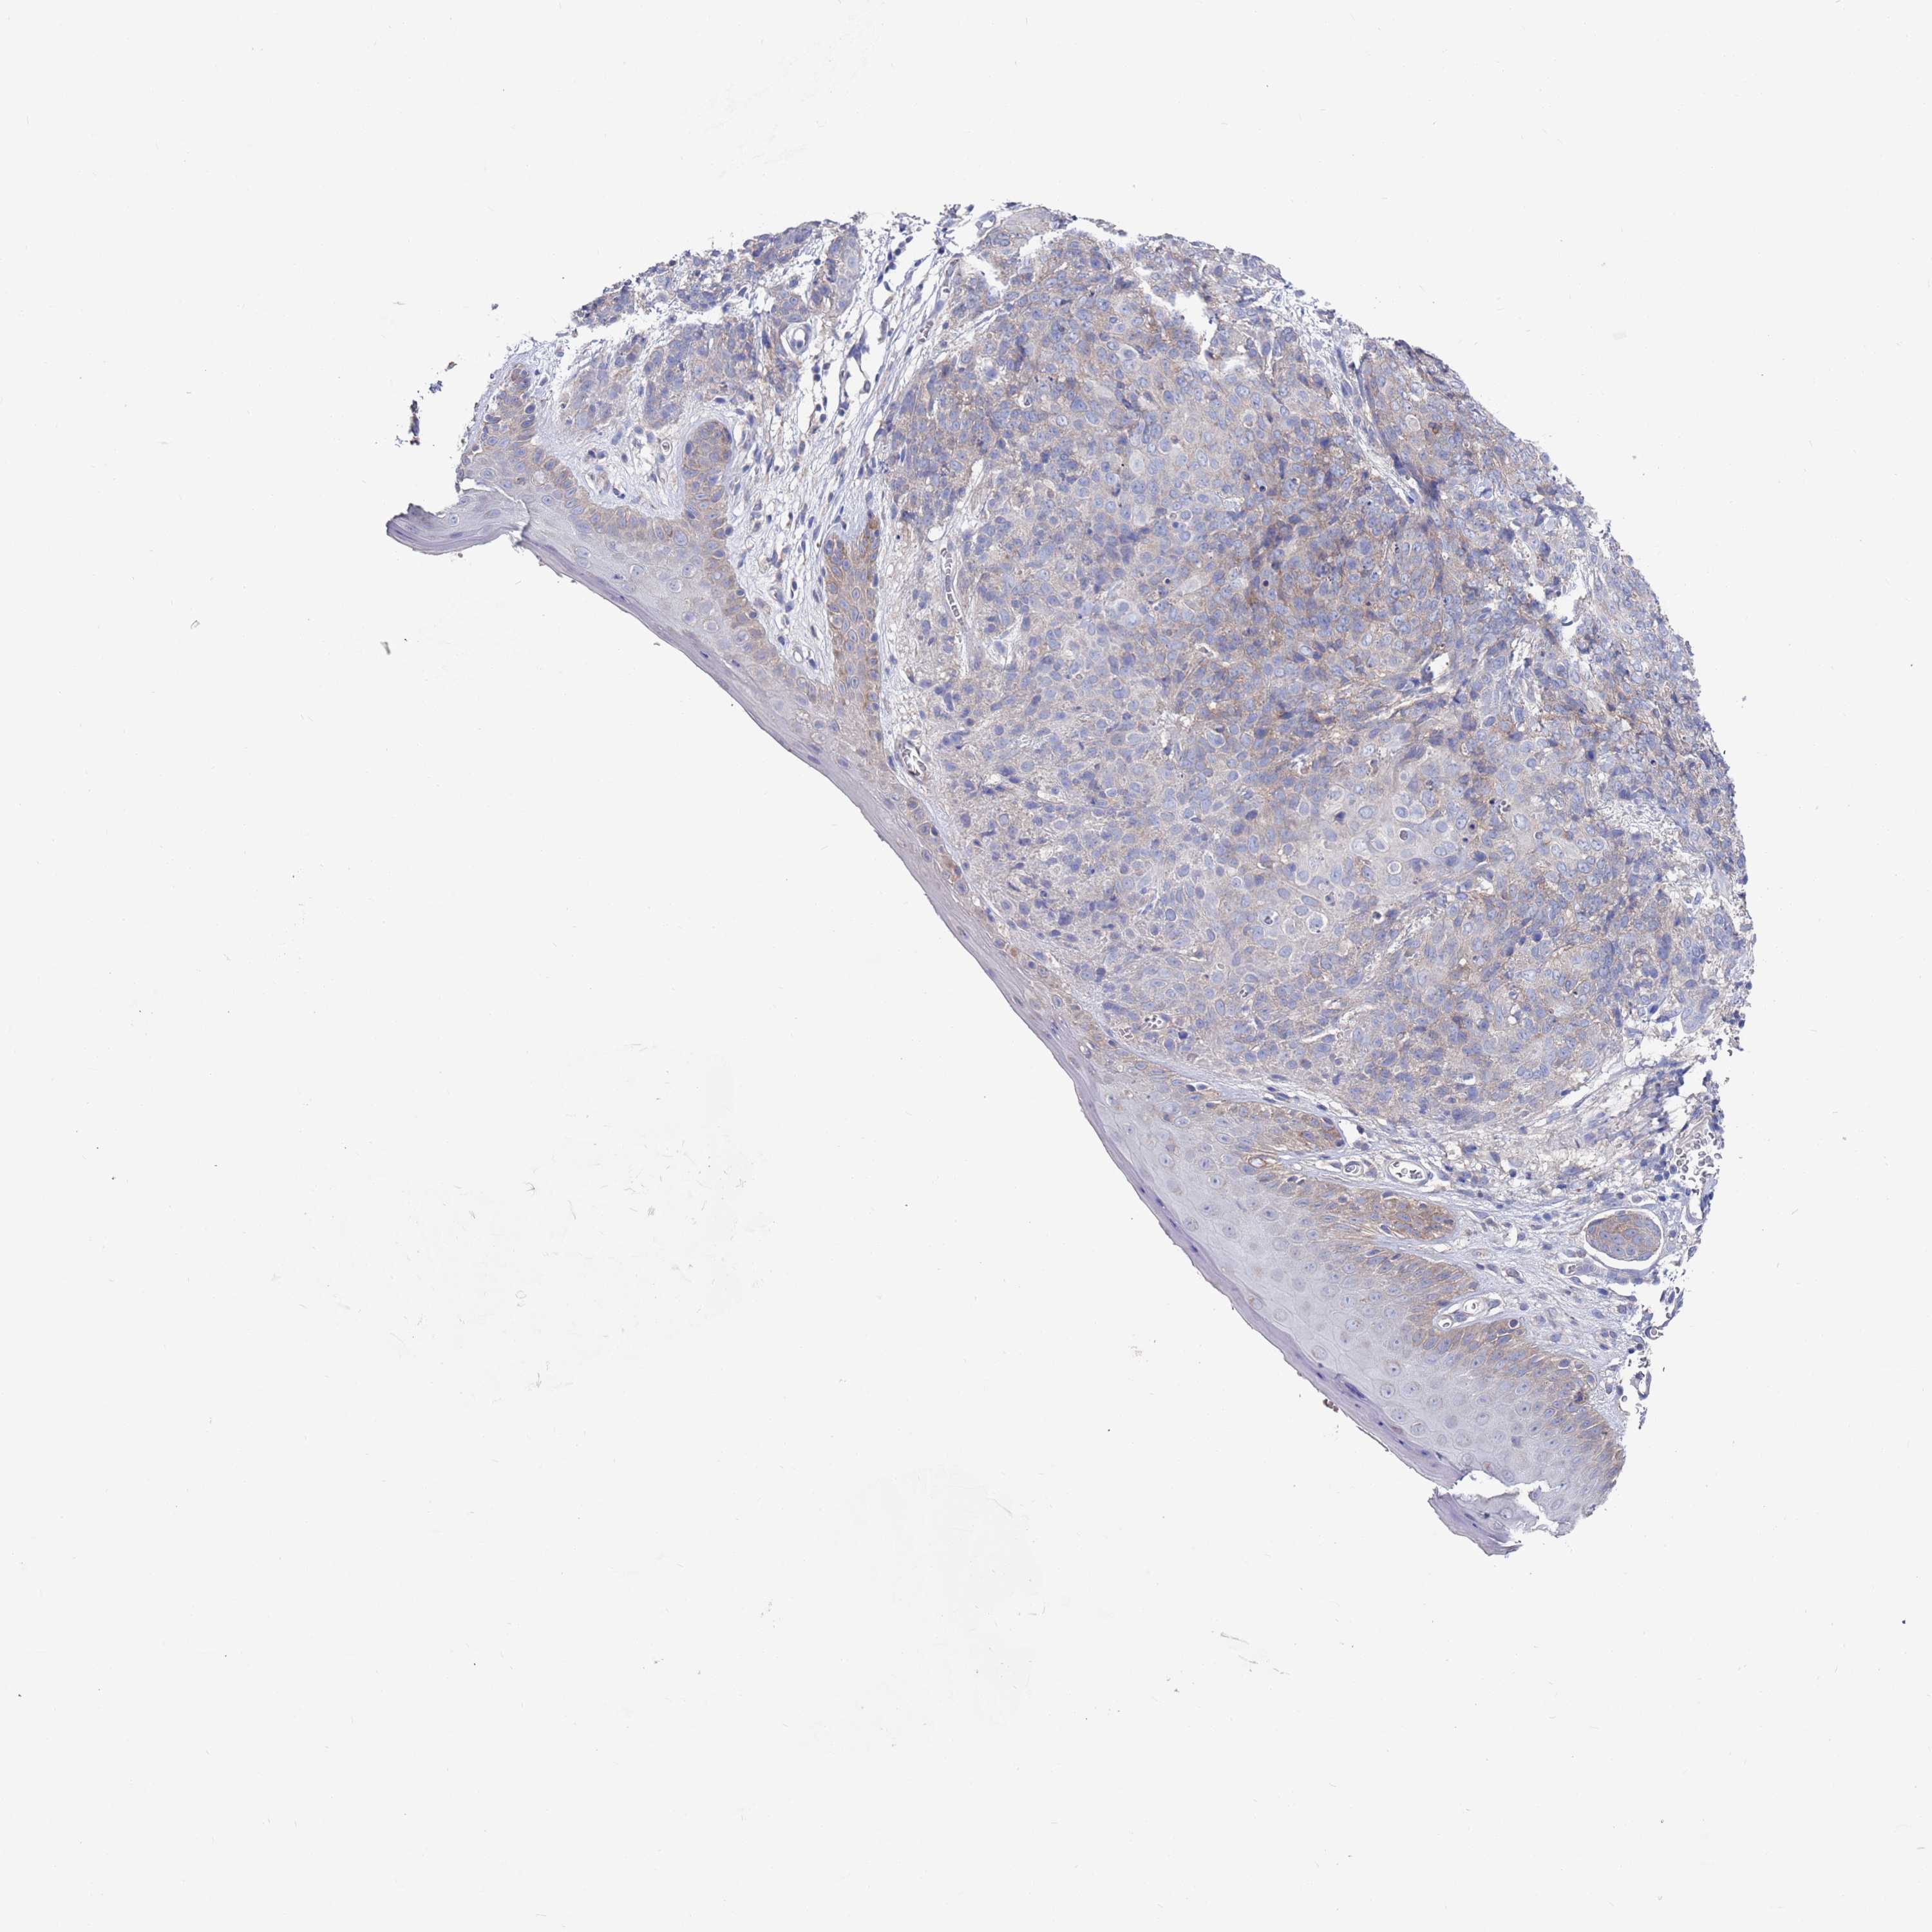

Basal cell and squamous cell cancer

SKIN CANCER - Protein expressioni

A mouse-over function shows sample information and annotation data. Click on an image to view it in a full screen mode. Samples can be filtered based on level of antibody staining by selecting one or several of the following categories: high, medium, low and not detected. The assay and annotation is described here.

Antibody stainingi

Antibody staining in the annotated cell types in the current human tissue is reported as not detected, low, medium, or high, based on conventional immunohistochemistry profiling in selected tissues. This score is based on the combination of the staining intensity and fraction of stained cells.

Each image is clickable and will lead to virtual microscopy that enables deeper exploration of all samples and also displays staining intensity scores, fraction scores and subcellular localization as well as patient and tissue information for each sample.

Antibody HPA047136

Staining

High

Medium

Low

Not detected

Intensity

Strong

Moderate

Weak

Negative

Quantity

>75%

75%-25%

<25%

None

Location

Nuclear

Cytoplasmic/membranous

Cytoplasmic/membranous,nuclear

Squamous cell carcinoma, metastatic, NOS